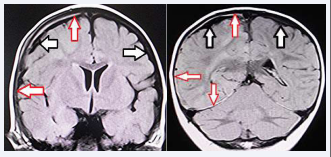

Magnetic resonance imaging (MRI) next day after operation disclosed thin, film-like, high-intensity hemorrhage surrounding the entire cerebral hemisphere (i.e holohemispheric hemorrhage), anatomically corresponding to dural border cell layer (Figure 3).

Figure 3 Magnetic resonance imaging (fluid-attenuated inversion recovery, axial view) next day after operation. Left & Right: Coronal View Thin, film-like, high-intensity hemorrhage surrounding the entire cerebral hemisphere (i.e holohemispheric hemorrhage), anatomically corresponding to dural border cell layer on the right side. (red arrows) Large subarachnoid space indicating benign enlargement of subarachnoid space. (black arrows). No primary cerebral parenchymal abnormality is observed.

Figure 3 Magnetic resonance imaging (fluid-attenuated inversion recovery, axial view) next day after operation.

Left & Right: Coronal View Thin, film-like, high-intensity hemorrhage surrounding the entire cerebral hemisphere (i.e holohemispheric hemorrhage), anatomically corresponding to dural border cell layer on the right side. (red arrows) Large subarachnoid space indicating benign enlargement of subarachnoid space. (black arrows).

No primary cerebral parenchymal abnormality is observed.

No primary cerebral parenchymal abnormality was observed. On the day after surgery, ophthalmological examination revealed bilateral retinal hemorrhage more on the right side.

A subdural collection may be described succinctly as an accumulation of fluid or blood within the dural border cell layer, which are very susceptible to disruption [10]. The MRI findings in the present case of a thin, film-like, high- intensity hemorrhage surrounding the entire cerebral hemisphere (i.e., the holohemisphere) presumably corresponded to the hemorrhage in the DBCL [12-15].

Particularly relevant here is thin-film like appearance seen after evacuation of ASDH may indicate hemorrhage localized in the DBCL. Based on the serial neuroimaging analysis, pathoetiology causing IASDH may be secondary spread of the hemorrhage from the DBCL into the subdural compartment [12]. Thus, some cases with IASDH may occur secondary to hemorrhage in DBCL without primary bridging vein rupture. Because the DBCL is easily disrupted, a hemorrhage originating in the inner dural plexus may be chiefly responsible for the non-traumatic situation or mild head impact [10].

Thin-film like appearance seen after evacuation of ASDH presumably shows hemorrhage localized in DBCL. The presence of HHDBCL in IASDH may make differential diagnosis from SBS/AHT, though requiring further discussion in future. In the present case, the intermediate- type IASDH located at inner part of the holohemispheric hemorrhage may indicate the secondary spread of the hemorrhage from the DBCL into the subdural compartment.